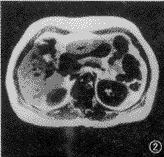

图1,2 患者 男,50岁。肝右叶大片脂肪浸润,不伴有占位病变。反相位序列(TR 128 ms,TE 2.7 ms,翻转角70°)示肝右叶下段低信号片状脂肪浸润(图1),而在同相位(TR 128 ms,TE 5.3 ms,翻转角70°)上呈等信号,无法区别(图2)